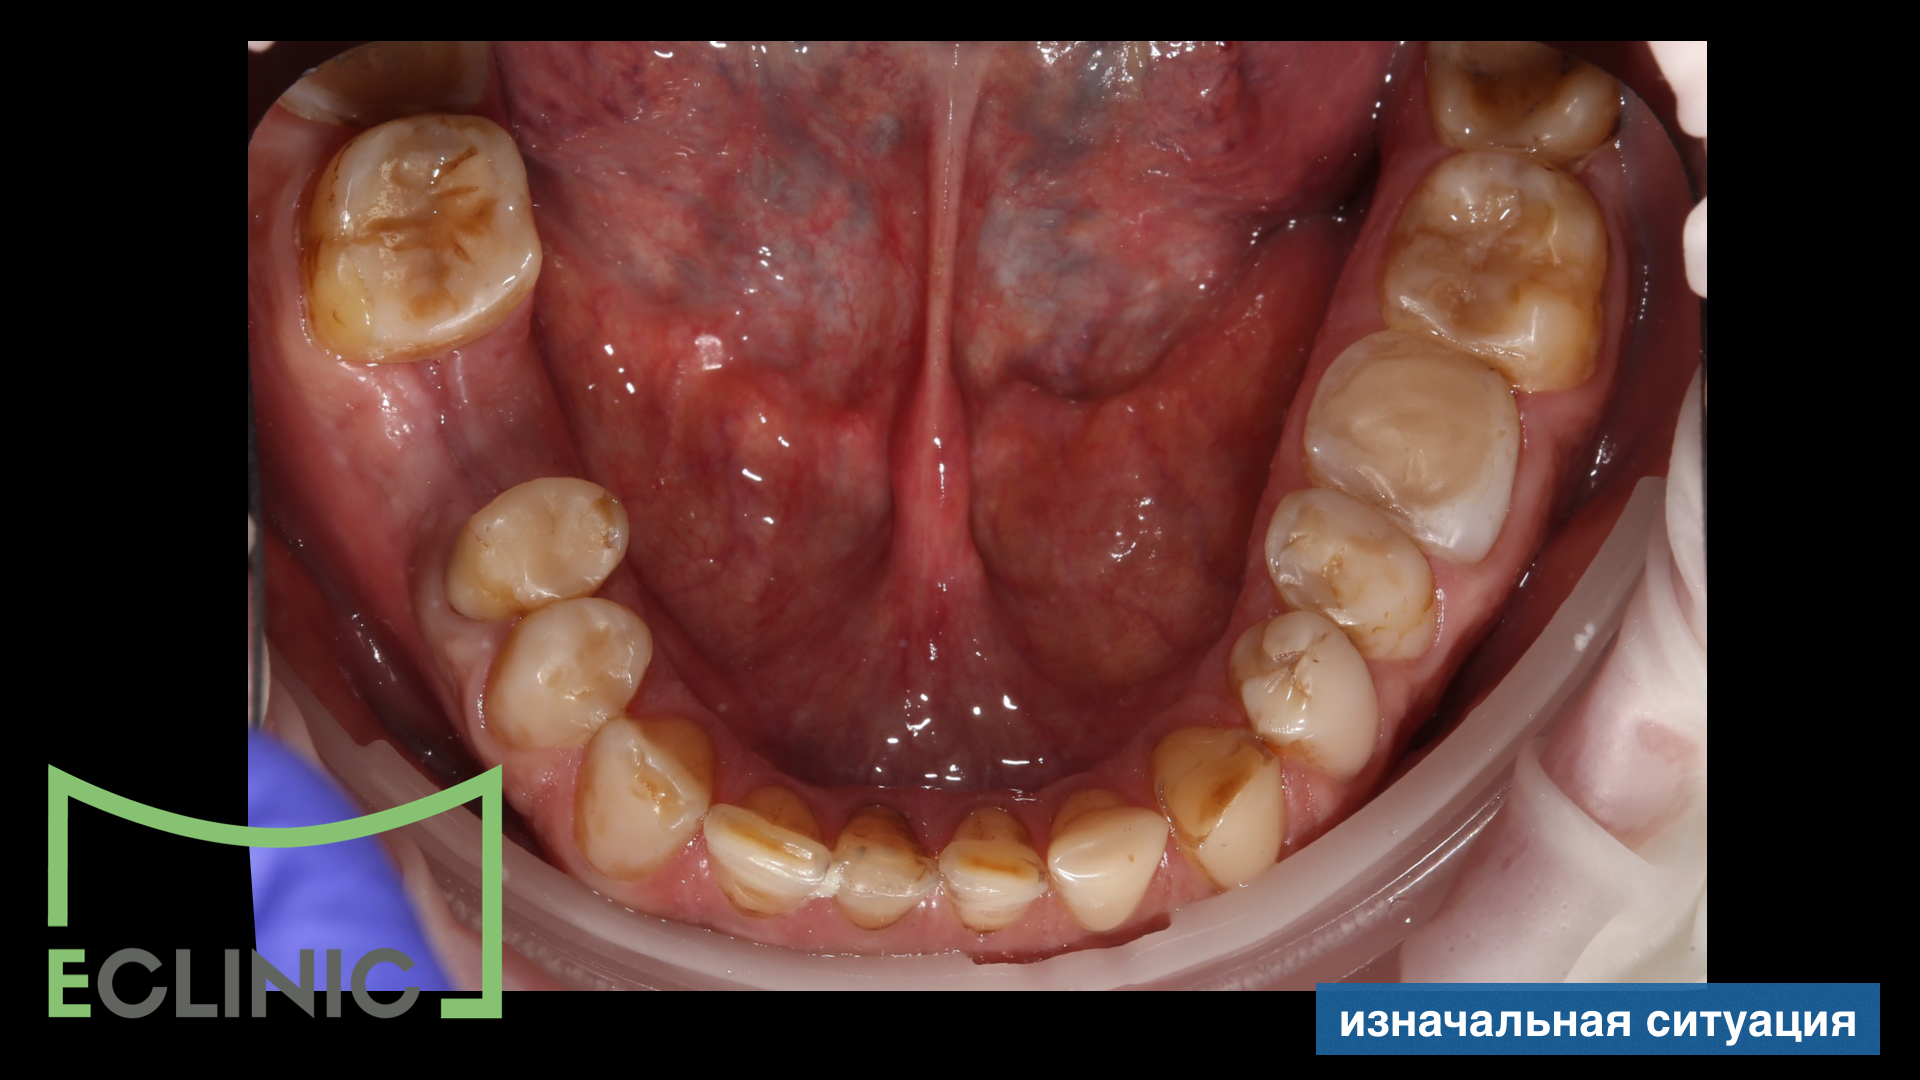

К нам в клинику обратился мужчина с желанием привести зубы в порядок

Совместно с хирургом был составлен план лечения, включающий имплантацию.

После окончания хирургического и эндодонтического этапов, для снижения мыщечного тонуса и восстановления комфортной позиции нижней челюсти была проведена сплинт терапия на миорелаксационной шине.